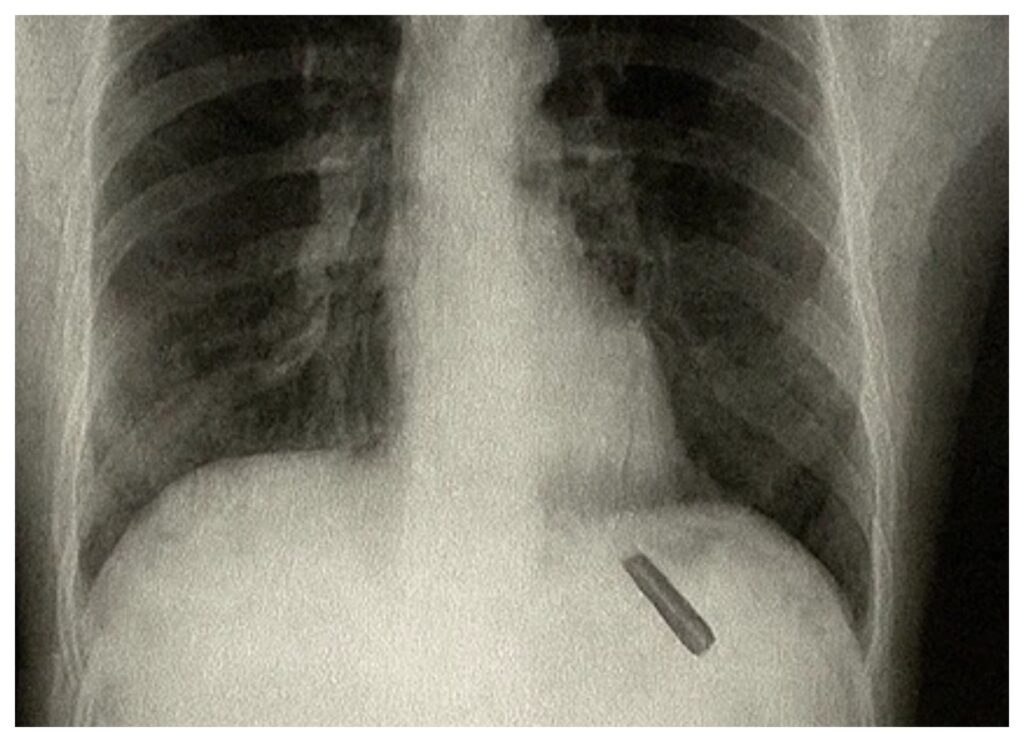

އޭނާގެ ފުއްޕާމޭގައި ގަލަމުގެ ދޯރިއެއް ތާށިވެފައި އިންކަން އެނގުނީ ޑޮކްޓަރުން އޭނާގެ އެކްސްރޭއެއް ނެގުމުންނެވެ. އަދި އެކަމުގެ ނުރައްކާ ބޮޑުކަމުން ވަގުތުން ސާޖަރީއެއް ހެދި ކަމަށްވެސް ނޫސްތަކުގައި ބުނެފައިވެ އެވެ.